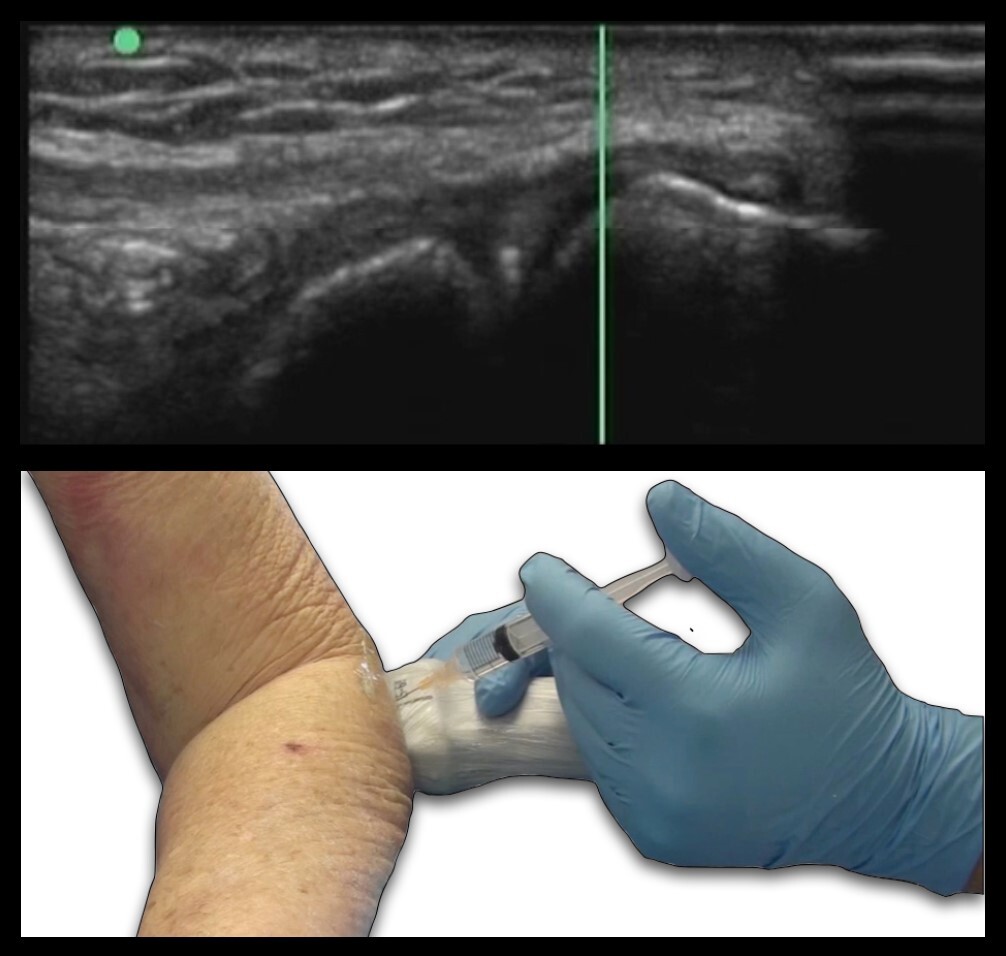

Elbow Radiocapitellar Joint Out of Plane Graphic and Image